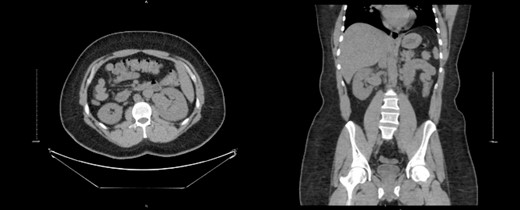

A 32-year-old male with no known chronic illnesses had a history of a motor vehicle accident five years ago, resulting in multiple bilateral rib fractures. An abdominal and pelvic CT scan conducted at the time did not reveal any other findings. The patient was admitted under the care of thoracic surgery for observation and pain management. After four years from the accident, the patient experienced intermittent right flank pain and made multiple visits to the emergency room. A CT scan of the kidneys, ureters, and bladder (CT KUB) was performed to rule out urolithiasis. The CT KUB showed multiple prominent structures with communication between the arterial and venous systems at the right renal hilum, suggestive of an intrarenal AVM with no apparent complications (Fig. 1). A CT run-off study confirmed the presence of an intrarenal AVM in the upper pole, measuring 2.9 cm (Fig. 2). The patient underwent angioembolization; however, multiple attempts at coil embolization failed due to the high risk of distal embolization. Subsequently, the patient underwent exploratory laparotomy for right AVF ligation. During the procedure, three AVF tracts were identified and ligated using clips. Prior to ligation, a thrill was palpable, but it was absent after the ligation. On the second postoperative day, a Doppler renal US was performed, which revealed patent right intrarenal arteries with normal resistive indices and normal peak systolic velocity in the right main renal arteries.

CT KUB showed multiple prominent structures with communication between the arterial and venous systems at the right renal hilum, suggestive of an intrarenal arteriovenous malformation (AVM).

Run-off computed tomography angiography (CTA) showed right kidney hilum tortuous vascular arteriovenous communication of the arterial and venous system represents intrarenal AVM towards the upper pole measuring 2.9 cm.